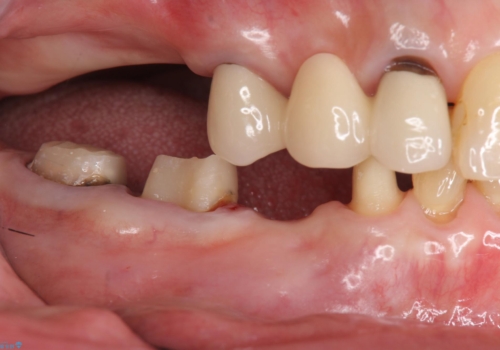

70代女性 状態の悪い歯を抜歯して、奥歯をブリッジに

- 他院で右下小臼歯が保存不可能と言われ来院。当院の判断でも残念ながら抜歯となり、欠損部は抜歯後ブリッジにしました。右下奥2本が連結されていたため、そこは各々切り離した形で被せ物のやり替えも行っています。

抜歯後3か月ほど仮歯で生活していただき、欠損部の歯肉の状態が安定してからブリッジを入れています。